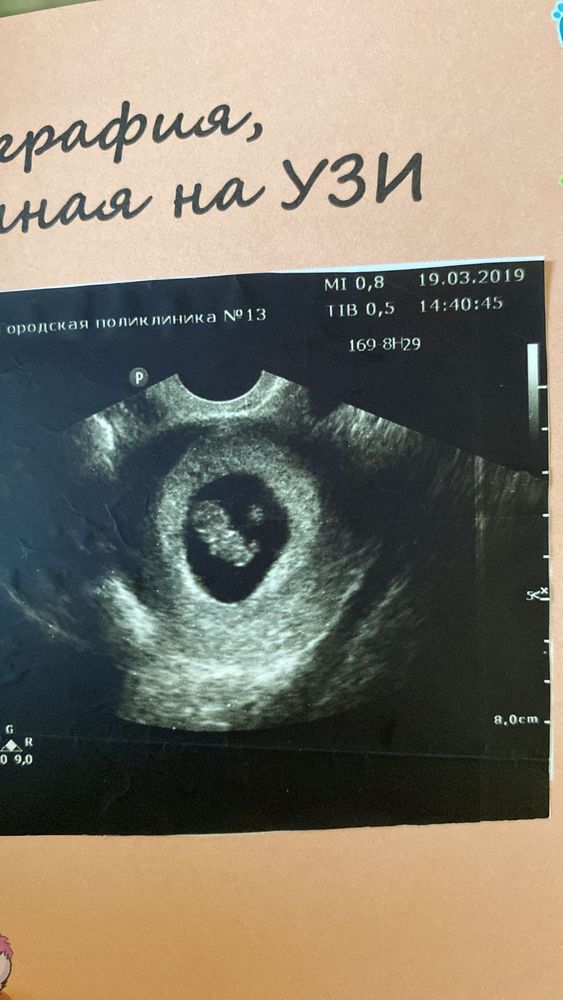

Изображение 8 недель моя доченька ей уже 4 года )